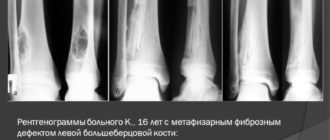

Метафизарная дисплазия млевой берцовой кости

Фиброзная дисплазия костей Фиброзная дисплазия костей – заболевание, при котором костная ткань замещается особой